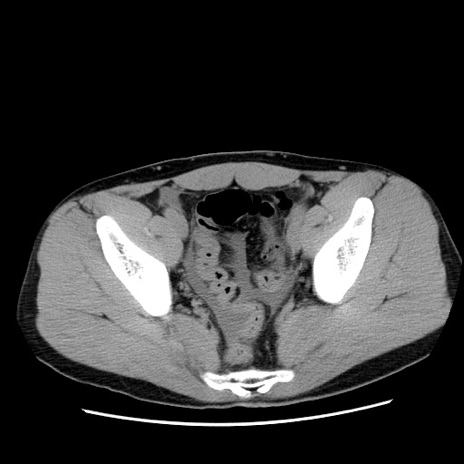

症例36(横断像)

【症例】20歳代 男性

【主訴】心窩部痛

【現病歴】今朝より上腹部痛あり。一旦軽快していたが再度出現したため救急要請。昨日夕に白身の魚を含む刺身を食べた。

【身体所見】BP 136/89mmHg、HR 74/min、BT 37.0℃、腹部:膨満、軟、心窩部に圧痛あり。反跳痛なし、筋性防御なし、腸雑音やや亢進あり。

【データ】WBC 17700、CRP 0.48